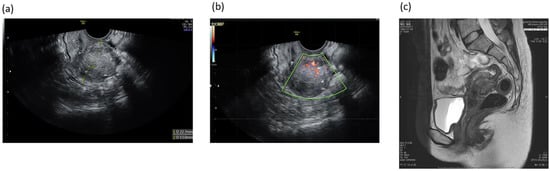

A Case of Elastography-Assisted Laparoscopic Fertility Preservation for Severe Deep Endometriosis Causing Ureteral Stenosis and Subtype II Adenomyosis

2. Case Presentation